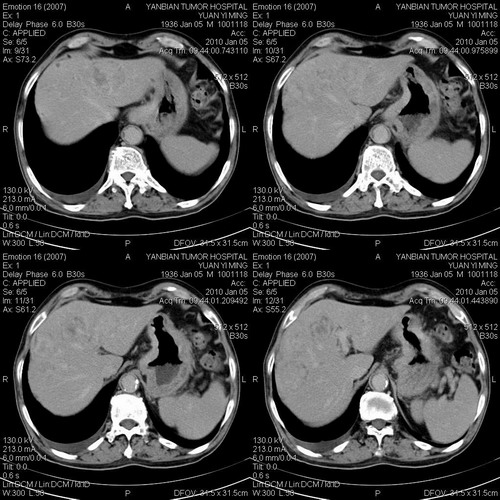

标题: CT24024:男,74岁。体检超声发现肝内多发占位性病变四天。 [打印本页]

标题: CT24024:男,74岁。体检超声发现肝内多发占位性病变四天。

1)考虑肝脏恶性肿瘤(转移瘤?)。2)肝外胆管轻度扩张。3)左肾小囊肿。

考虑转移瘤。

考虑肝脏恶性肿瘤(转移瘤?)。2)肝外胆管轻度扩张。3)左肾小囊肿。